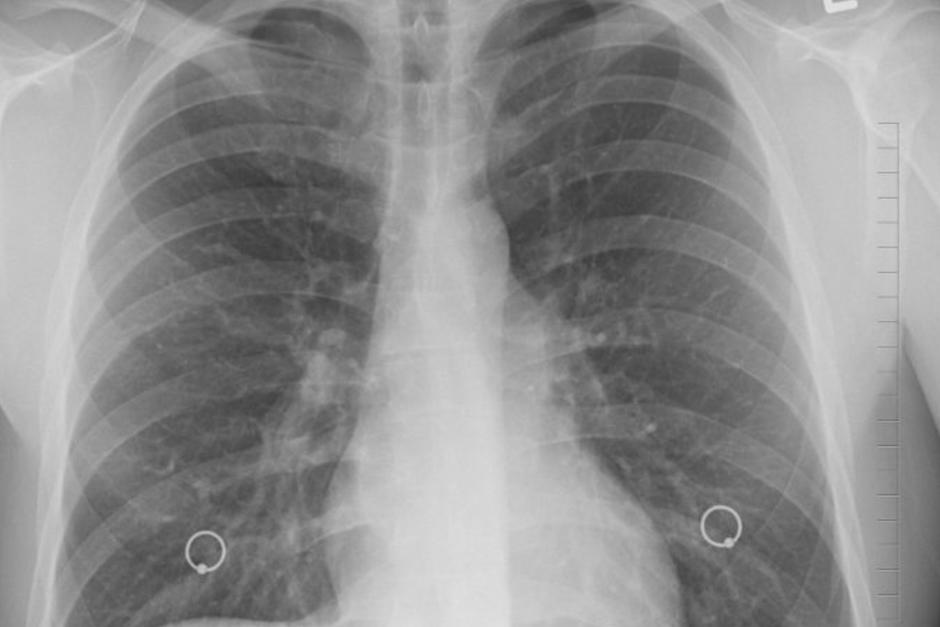

La especialista comparó en redes sociales las radiografías de pulmones de pacientes normales, de pacientes con Covid-19 y de fumadores, el resultado es alarmante.

“Los pulmones post-covid se ven peor que cualquier tipo de pulmón de fumador que hayamos visto y colapsan y se coagulan y la falta de aire persiste y no para”, afirmó Brittany Bankhead-Kendall, profesora asistente de la Universidad Técnica de Texas.

La doctora, quien trató a cientos de pacientes con Covid-19, advierte que entre el 70% y 80% de los infectados asintomáticos experimentan un daño similar a sus pulmones: “Todavía hay personas que dicen ‘Estoy bien. No tengo ningún problema’ y cuando les haces una radiografía de tórax se ve realmente mal”.

Look at this comparison of the lungs from a healthy person, a smoker, and someone with COVID-19. Our society shares wide concerns over smoking. This should be echoed by unified passion to beat the coronavirus. Notice the differences here… pic.twitter.com/OksGqH1OZ9